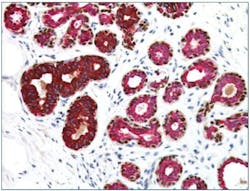

It can be challenging to distinguish ductal carcinoma in situ (DCIS) from invasive breast cancer by H&E stains alone. The utility of myoepithelial markers can be attributed to the fact that these markers should still be contained within ducts in DCIS, whereas the myoepithelial cell layer and basement membrane would have been breached in invasive carcinoma, no longer intact, and not stained in IHC. Typical myoepithelial markers include smooth muscle actin (SMA), calponin, p63, and smooth muscle myosin heavy chain (SMMHC).4 High-molecular-weight cytokeratins (CKs), such as CK14 and CK5/6, are relatively specific to myoepithelial cells; although, some of the CKs are also expressed in some invasive breast cancer such as basal-like.5 Jain et al. (2011) reported reduced interobserver and intraobserver variability in the diagnosis of atypical ductal hyperplasia using a cocktail of CK5, CK14, p63, CK7, and CK18 and demonstrated how IHC biomarkers multiplexing may benefit management of these cases.6 (Figure 1)7 The list of myoepithelial markers keeps growing, but there could be significant variation in sensitivity and specificity. One must exercise caution when interpreting the loss of myoepithelial markers, supported by abnormal morphologies in H&E slides.8